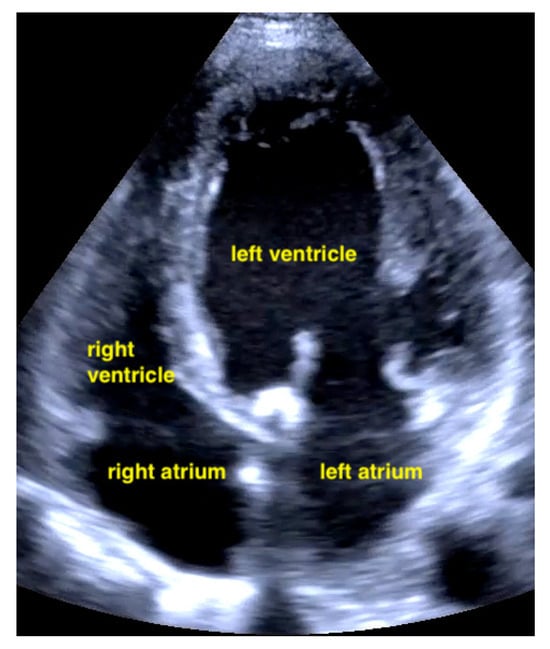

7.2.1. Pericardial Effusion

Pericardial effusions are best identified with a convex or sector probe in the subxiphoid or parasternal view. While it is important to simply note whether an effusion is present, sonographic and clinical (hypotension and tachycardia) evidence of cardiac tamponade should be sought. These include diastolic collapse of the right atrium free wall, followed by free wall collapse of the right ventricle as tamponade worsens. Both the apical and subcostal four-chamber views are ideal for this assessment. However, the subcostal window allows for a rapid transition to the proximal IVC view, which is dilated (>2 cm) and does not vary with respiration in cases of cardiac tamponade. Although many cases of medium and large pericardial effusions are obvious on ultrasound, there are notable exceptions. These include some hemorrhagic effusions which show significant coagulation, thus appearing echogenic on ultrasound, leading to frequent confusion with an epicardial fat pad or even a portion of the myocardial wall. Conversely, some epicardial fat pads may be confused with pericardial effusions, especially by novices. Differentiating between the two is easy by using anatomical knowledge. An epicardial fat pad does not extend enough inferiorly to be seen on a longitudinal IVC inlet view, while a pericardial effusion will in virtually all cases (Figure 7, Figure 8, Figure 9 and Figure 10).

Figure 9.

Pericardial effusion in apical four chamber view compresses the right atrium slightly (RA = right atrium, LA = left atrium, RV = right ventricle, LV = left ventricle).